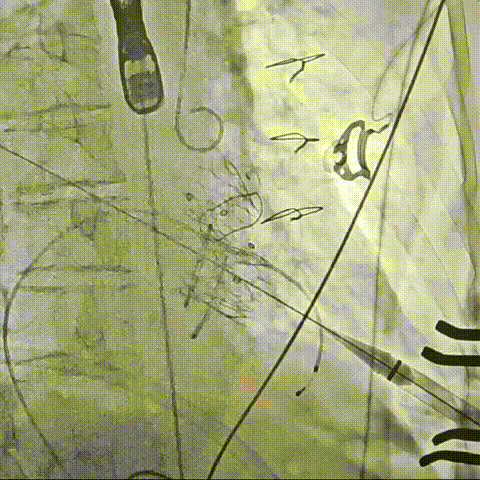

Part3: EVAR

EVAR